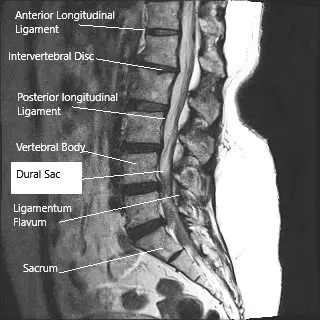

Sagittal section (MRI) of the lumbar spine showing dural sac.

How the Body Part Normally Works? (Relevant Anatomy)

The dura is the tough, protective outer membrane surrounding the brain and spinal cord. It contains cerebrospinal fluid, which serves as a cushion and delivers nutrients to nerve tissues. Underneath the dura are finer membranes (arachnoid and pia mater) that further protect the spinal cord. When the dura is torn, CSF leaks out, lowering pressure in the brain and spinal canal. This can lead to postural headaches (worse when standing), dizziness, and nausea.